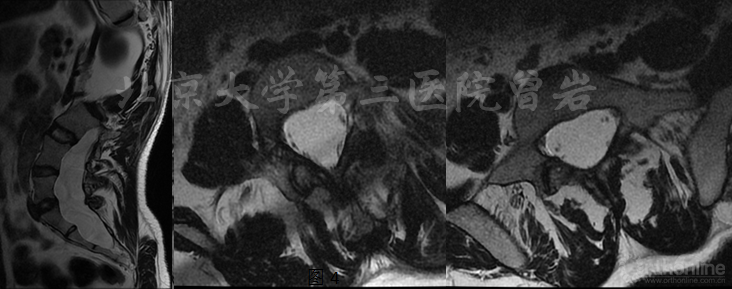

MRI(图8):显示腰骶段椎管扩大,硬膜囊扩张。

图8